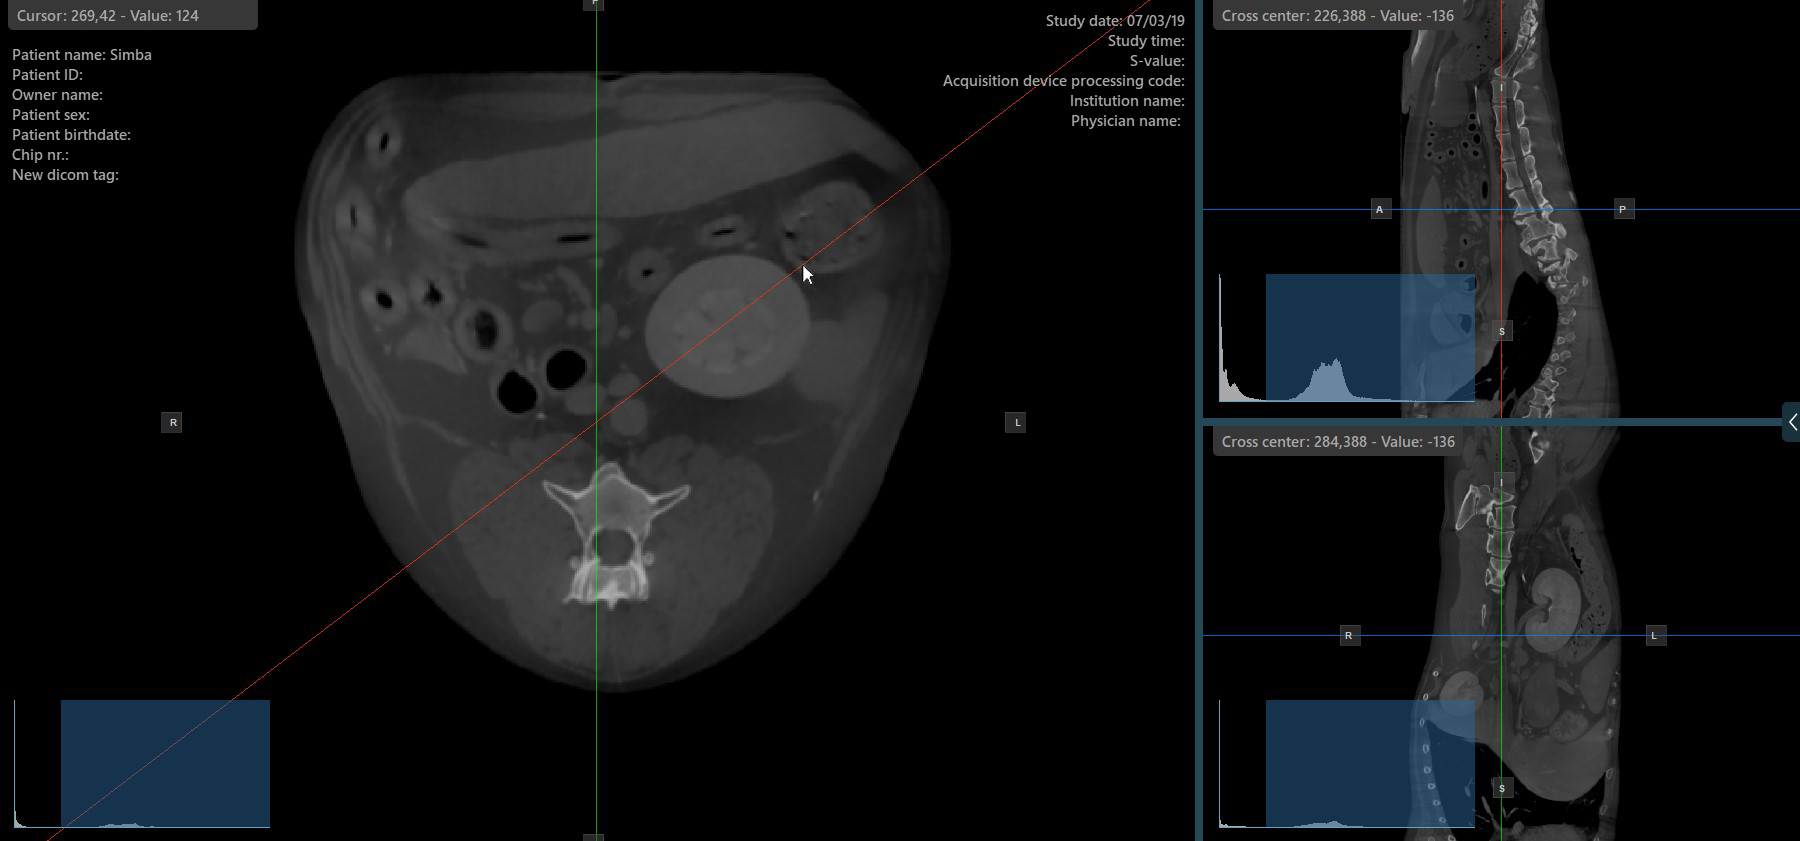

Szeletelő rotációjának módosítása¶

A szeletelő rotációjának módosítása megváltoztatja a megfelelő kép síkjainak orientációját. Az egyes szeletelők kiválaszthatók a Elem kijelölése (Alapértelmezett) eszközzel, amely alapértelmezés szerint a jobb egérgombhoz van rendelve.

Miután a konkrét szeletelő ki van választva, húzza a szeletelőt a kívánt irányba a forgatáshoz. A megfelelő kép síkjának orientációja ennek megfelelően változik.